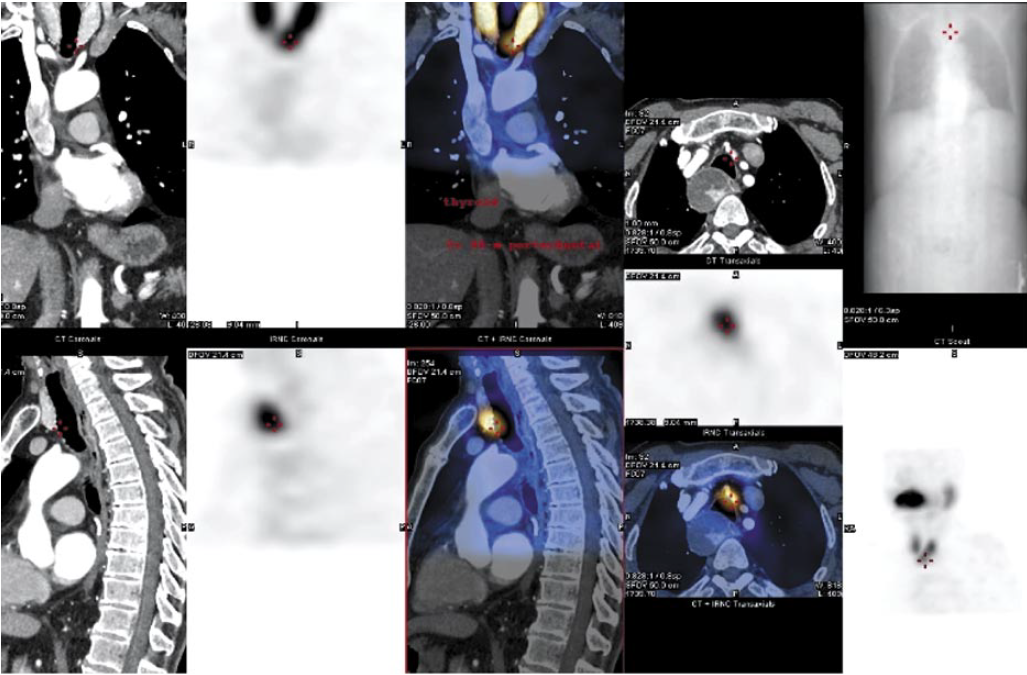

Основываясь на данных лабораторной диагностики, для исключения аденомы околощитовидных желез мы выбрали как наиболее информативный метод топической диагностики cцинтиграфию с 99mTc-пертехнетатом [7, 8]. Полученные результаты явились наиболее характерными для аденомы околощитовидной железы, эктопированной в заднее средостение (рис. 6).

Рис. 6. Результат сцинтиграфии с 99mTc-пертехнетатом.

Fig. 6. The result of scintigraphy with 99mTc-pertechnetate.

Дополнительно при проведении данного исследования выявлены очаги, характерные для вторичного (метастатического) поражения костей скелета (очаги гиперфиксации радиофармпрепарата в правой плечевой кости, в свободном крае XI ребра). Предположительно, такого рода изменения в костной структуре при выраженном гиперпаратиреозе могут являться зонами остеосклероза, что подтверждено исследованием метаболического изменения костной ткани: остекальцин – 178 (14–46 нг/мл), Beta-Cross Laps – 0,845 (<0,854 нг/мл).